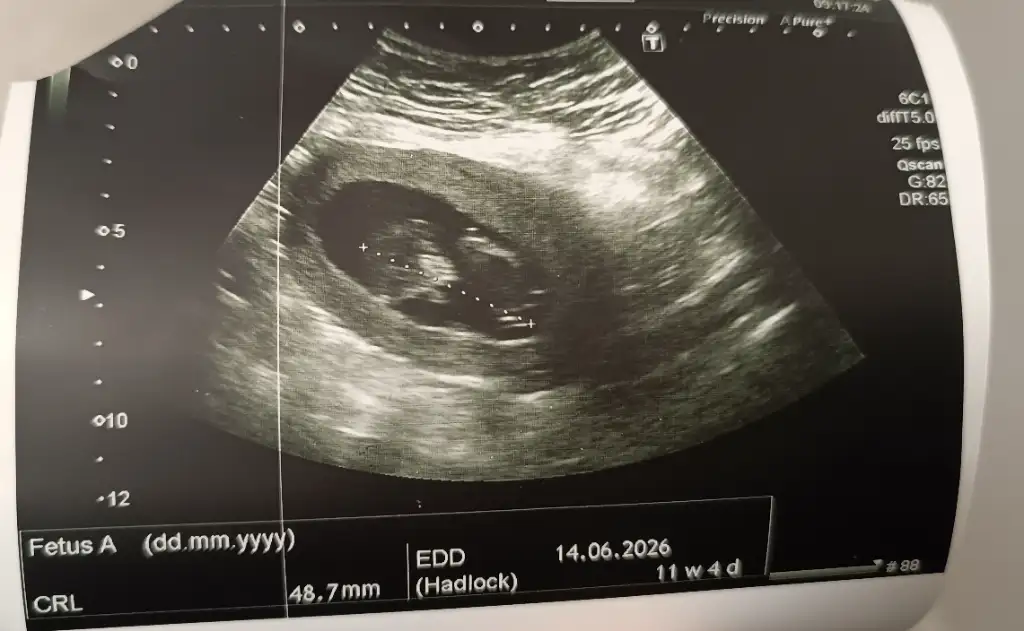

• IMG_20251127_101317.webp

IMG_20251127_101317.webp

32,9 KB · Görüntüleme: 31